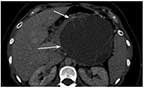

The Case:The patient is an otherwise healthy 45-year-old female who presented to her primary care physician with 6 weeks of increasing left upper quadrant abdominal pain with radiation to the back. She underwent an abdominal ultrasound, which revealed a large cystic abdominal mass. Subsequent abdominal CT and MRI results confirmed a large 12 × 13-cm complex cystic mass arising from the tail of the pancreas, with multiple septations, peripheral calcifications, and septal enhancement (Figure 1). The patient’s imaging also showed chronic occlusion of the splenic vein with extensive collateral formation. Pertinent labs included a hemoglobin level of 11.2 g/dL and a white blood cell count of 19.6 × 106/L, with 93% neutrophils. Blood chemistries were normal; the serum albumin level was 3.3 g/dL; carbohydrate antigen 19-9 (CA 19-9) level was elevated at 84 U/mL. Cyst fluid sampling revealed an amylase level of 25 U/L.

FIGURE 1

The Patient's 13-cm Mucinous Cystic Neoplasm Is Indicated by Arrows.